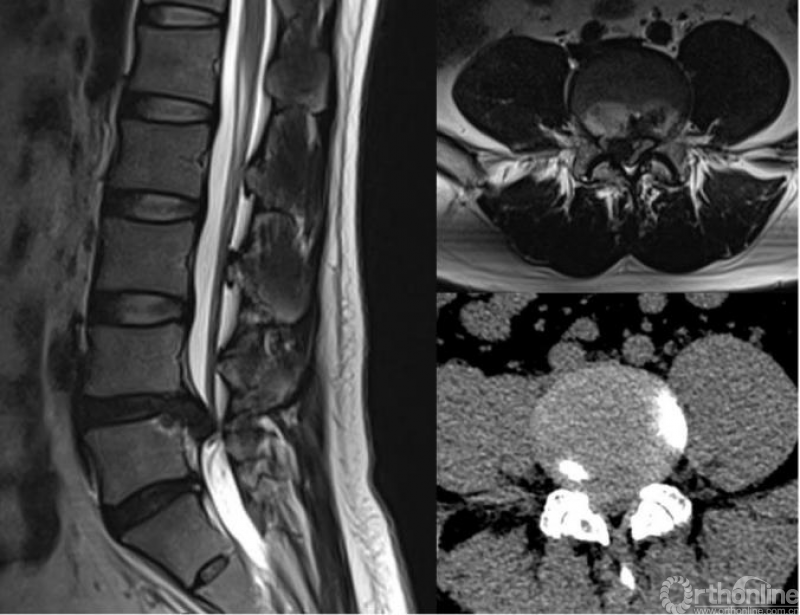

入院后查体:患者腰椎活动受限,右侧直腿抬高试验30度(+),加强试验(+),病理征(-),无肌力及感觉障碍,右下肢VAS评分8分。完善相关检查,结合术前影像学检查(图1)提示为,腰4-5巨大椎间盘脱出。

图1.患者术前影像学(CT+MRI)检查结果